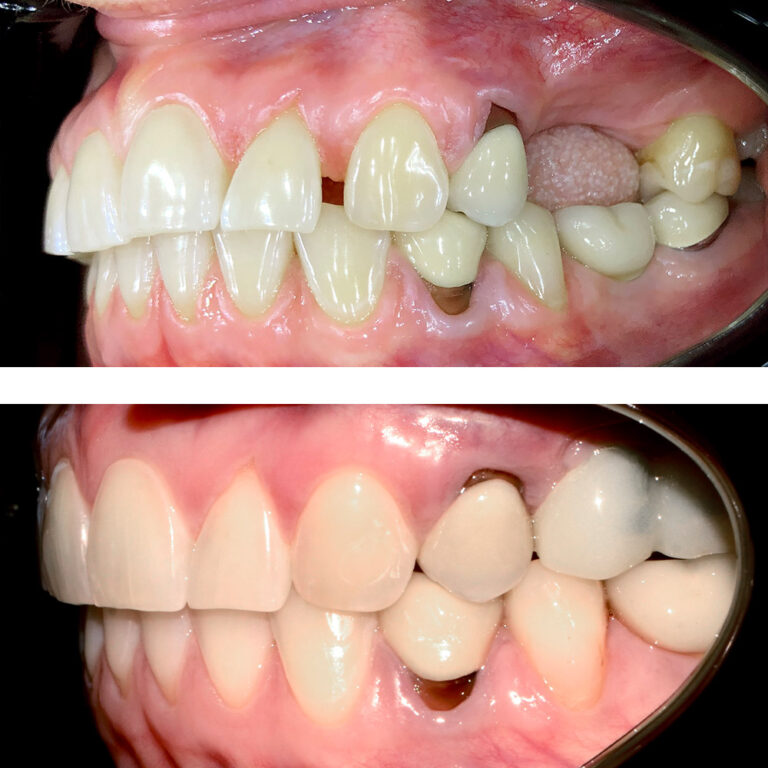

Кейс 23

Иванова Екатерина Сергеевна

Количество кап ВЧ 24

Количество кап НЧ 24

ДО

ПОСЛЕ